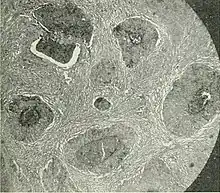

| Barthlin carcinoma tissue cross section | |

Bartholin gland can be differentiated by histology to determine whether the malignancy is due to squamous cell carcinoma, adenoid cystic carcinoma, or adenocarcinomas.[5]